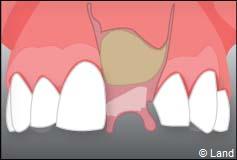

Le chirurgien-dentiste après une anesthésie locale pratique une incision, puis il décolle la gencive pour accéder à l’os alvéolaire.

Ensuite il prépare l’emplacement de l’implant dans l’os en passant plusieurs forets de diamètre croissant. Le forage de l’os se fait à vitesse maîtrisée et lente sous irrigation, pour respecter la structure osseuse et éviter tout échauffement de celle-ci. Le praticien arrête lorsqu’il a obtenu un puits d’un diamètre très légèrement inférieur à l’implant à poser.

L’implant est placé dans l’os le plus souvent par vissage et doit avoir une liaison forte avec l’os. Le praticien replace alors la gencive et pose des points de suture.